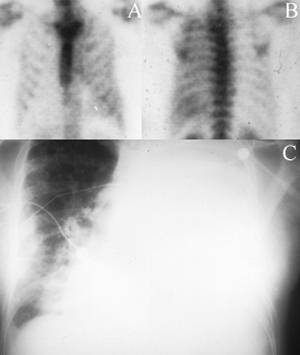

Pleural EffusionMalignant pleural effusion

Anterior (A) and posterior (B) bone scintigrams show generalized increased radionuclide accumulation in the left hemithorax in this patient with lung carcinoma. A chest X-ray (C) confirms the presence of a left-sided pleural effusion.